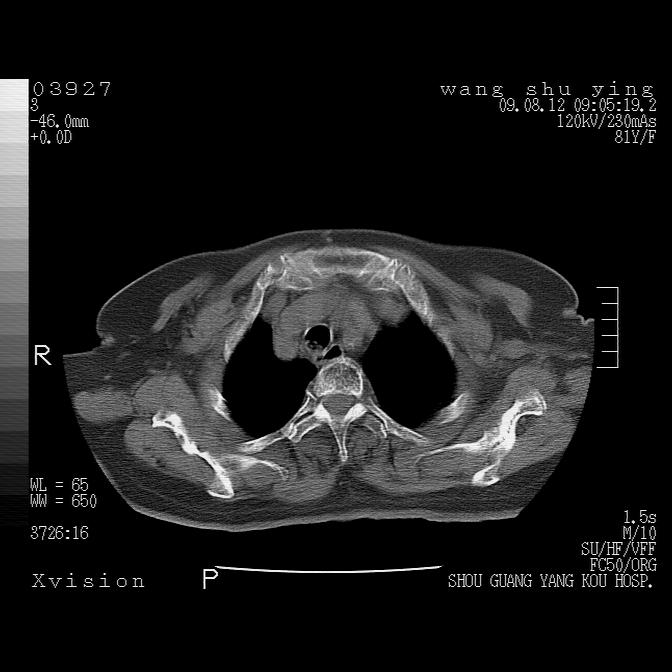

以下是引用帅河马在2009-8-12 12:59:00的发言:[br]两肺感染性病变伴双侧胸膜肥厚。[br]左侧甲状腺腺瘤不除外。[br]腹水+心包积液。[br][br][本贴已被 帅河马 于 2009-8-12 13:14:32 修改过]

以下是引用sdzyy在2009-8-12 18:17:00的发言:[br]两肺感染性病变伴双侧胸膜肥厚。[br]左侧甲状腺腺瘤不除外。[br]腹水+心包积液。[br]支持

以下是引用随光逐影在2009-8-12 19:42:00的发言:[br]1)两肺感染性病变伴双侧胸膜肥厚。2)不排除左侧甲状腺腺瘤。3)肝脏占位性病变;建议行进一步检查。